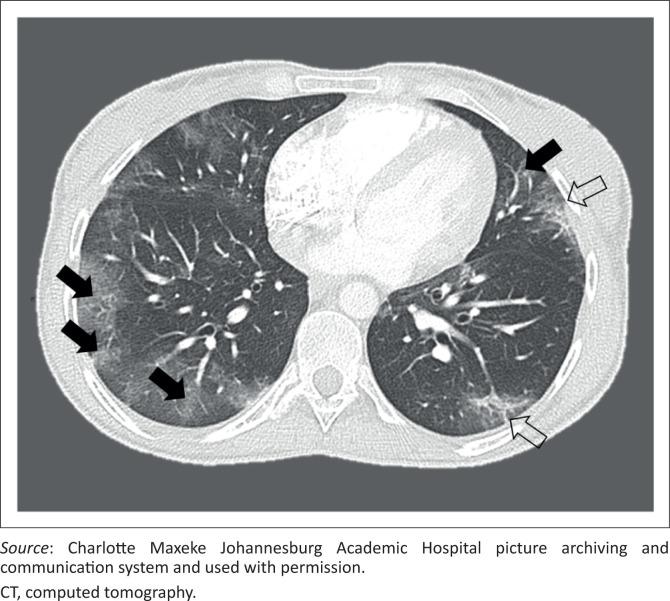

A total of 113 adult patients with a mean age of 46 years and 10 months were included. A total of 113 chest radiographs and six CTs were read. Nineteen patients were HIV-positive (16.8%), 40 were hypertensive and diabetic (35.4%), respectively, and one had TB (0.9%). Common symptoms included cough ( = 69; 61.6%), dyspnoea ( = 60; 53.1%) and fever ( = 46; 40.7%). Lower zone predominant ground glass opacities (58.4%) and consolidation (29.2%) were most frequent on chest radiographs. The right lower lobe was most involved (46.9% ground glass opacities and 17.7% consolidation), with relative sparing of the left upper lobe. Bilateral ground glass opacities (66.7%) were most common on CT. Among the HIV-positive, ground glass opacities and consolidation were less common than in HIV-negative or unknown patients ( = 0.037 and = 0.05, respectively).

COVID-19 in South Africa has similar chest imaging findings to those documented globally, with some differences between HIV-positive and HIV-negative or unknown patients. The authors corroborate relative sparing of the left upper lobe; however, further research is required to validate this currently unique local finding.